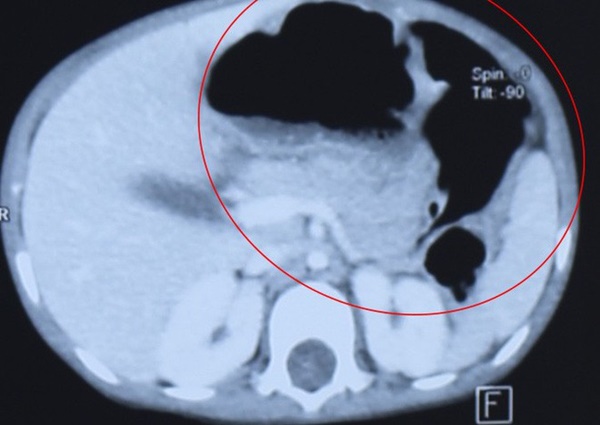

Hình ảnh chụp chiếu trong dạ dày bé P. và phát hiện bệnh lý tắc tá tràng hiếm gặp.

Tại đây, các bác sỹ tiến hành thăm khám, chụp chiếu thì phát hiện dạ dày bé P. giãn to đến tá tràng. Các bác sỹ sau đó đã chẩn đoán bé P. bị tắc tá tràng không hoàn toàn do màng ngăn niêm mạc.